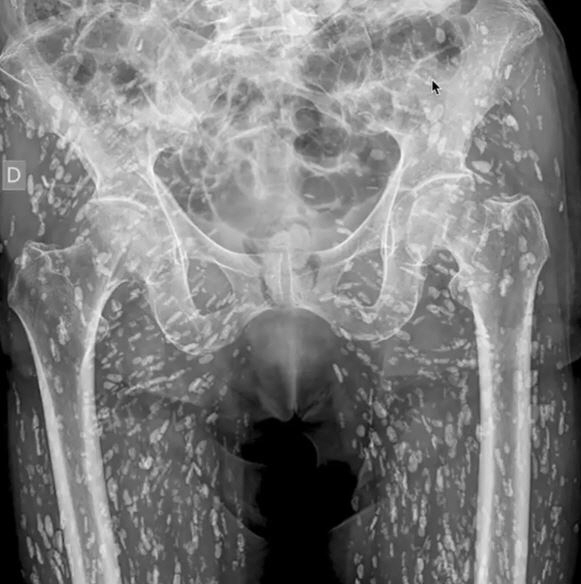

데일리스타 등 외신들에 따르면 미국 플로리다 의대병원 샘 갈리 교수는 최근 자신의 SNS에 "내가 본 것 중 가장 미친 X-레이"라며 사진 한 장을 게시했다.

샘 교수는 "환자가 병에 대해 전혀 알지 못했으며, 고관절 통증을 느낀 후에야 검사를 받으러 왔다"고 했다.

이 결절의 정체는 '낭미충증(Cysticercosis)'이었다.

샘 교수는 "이 낭종은 몸 전체의 어느 곳으로든 이동할 수 있으며, 엉덩이와 다리의 근육 및 연조직에도 치명적으로 침투할 수 있다"면서 "골반에만 있다면 생명을 위협하는 문제를 일으키지 않는데 문제는 그것들이 뇌로 이동할 수도 있다는 것이다"고 설명했다.

그럴 경우 두통, 혼란, 발작 및 심지어 사망과 같은 치명적 상황이 벌어질 수 있다.